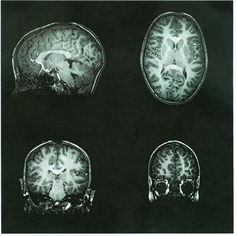

铅中毒会影响孩子的认知发育。

在大脑中,铅可以破坏神经元细胞内线粒体的功能,从而使得细胞不能正常运转。它也可以影响神经递质(神经元间通信的物质)的传递并改变大脑中血管的结构。综上所述,这种损伤可能会导致智商下降、学习障碍、生长减缓、多动症和缺乏对冲动的控制力,甚至是听力障碍。这就是为什么大家特别关注儿童铅中毒的问题。